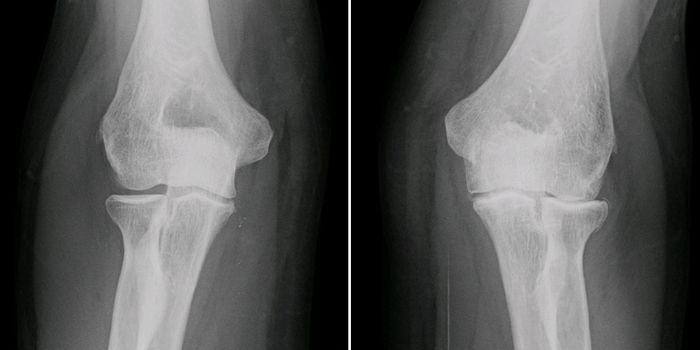

NOV 29, 2022Drug Discovery & DevelopmentVitamin K1- a nutrient found in leafy greens like kale, cabbage, and spinach- may help reduce bone fracture risk in elde ...